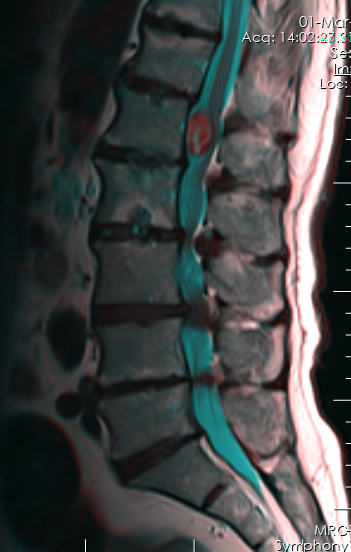

Διάγνωση Απαραίτητες είναι: Η λεπτομερής λήψη ιστορικού και η κλινική εξέταση, Η μαγνητική τομογραφία του μέρους της σπονδυλικής στήλης όπου εντοπίζεται κλινικά η εξεργασία, Σε εξεργασίες που επηρεάζουν το οστό: η αξονική τομογραφία (με τρισδιάστατη ανασύνθεση) του μέρους της σπονδυλικής στήλης όπου εντοπίζεται κλινικά η εξεργασία, Σε ορισμένες περιπτώσεις: Το σπινθηρογράφημα των οστών, Η ογκολογική διερεύνηση όταν υπάρχει υποψία δευτεροπαθούς εντόπισης (απεικονιστικός και αιματολογικός έλεγχος), Η οσφυονωτιαία παρακέντηση (λήψη εγκεφαλονωτιαίου υγρού από την σπονδυλική στήλη για ανεύρεση παθολογικών κυττάρων). |